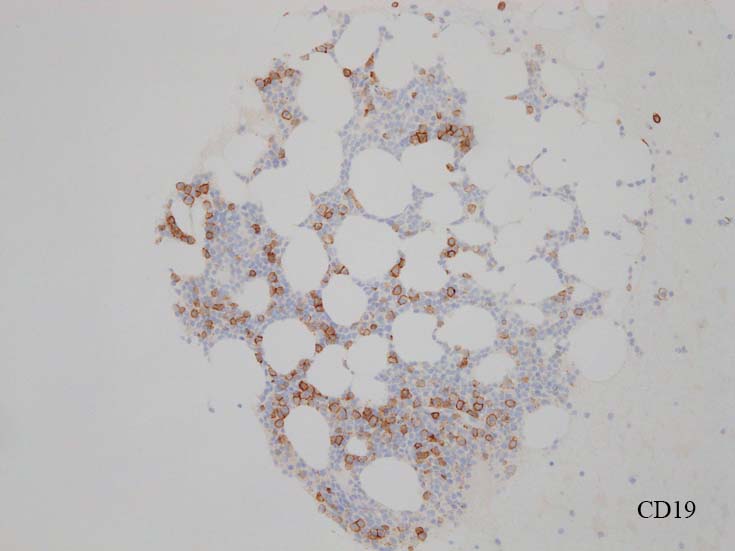

blastic cellsは, CD45+, CD34+, CD38+, TdT+, CD7+, HLA-DR+, CD123+. cCD3-, sCD3-(FCM), CD20-, CD19-とCD79a-(?) (plasma cellが陽性でIHCでは判定が難しい), MPO-.

CD138陽性細胞が増加している. CD19陽性細胞が多く認められ, 明かなkappa, lambda restrictionは見られない. polyclonal proliferationと考えられる.